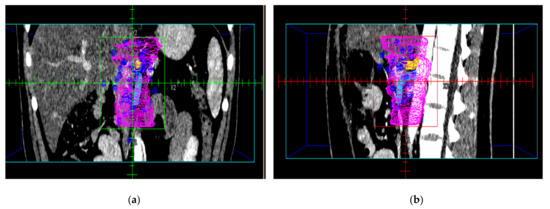

3. Results

4. Discussion